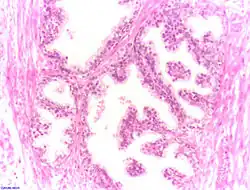

Epiteliul secretor este în mare parte pseudostratificat, fiind format din celule columnare și bazale, ce sunt susținute de o stromă fibroelastică ce conține mici fibre musculare. Epiteliul este foarte variabil, prezentând zone cu celule cuboidale sau cu celule scuamoase, în special în zonele distale și a canalelor[2]. Prezentă în interiorul prostatei, uretra (uretra prostatică) se unește cu cele două canale ejaculatoare.

Sunt două forme clinice: prostatită acută, caracterizată prin edem și infiltrație granulocitară interstițială însoțită de cele mai multe ori de colecții purulente și prostatită cronică, caracterizată prin scleroza țesutului interstițial, atrofie a epiteliului, de cele mai multe ori cu proliferări papilifere.